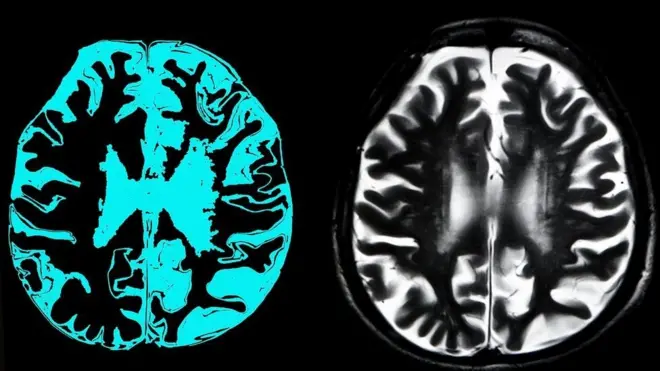

Kaynak, Getty Images